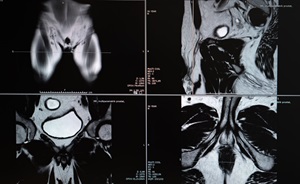

High-resolution MRI has been a game changer for diagnosing prostate cancer and preventing unnecessary biopsies.

Following PSA blood, biomarker and imaging tests, your doctor may recommend a biopsy of some prostate tissue. Hackensack Meridian Health is the first center in the area to offer MRI-targeted fusion biopsy. This advanced approach combines real-time ultrasound and MRI images for exceptional accuracy.